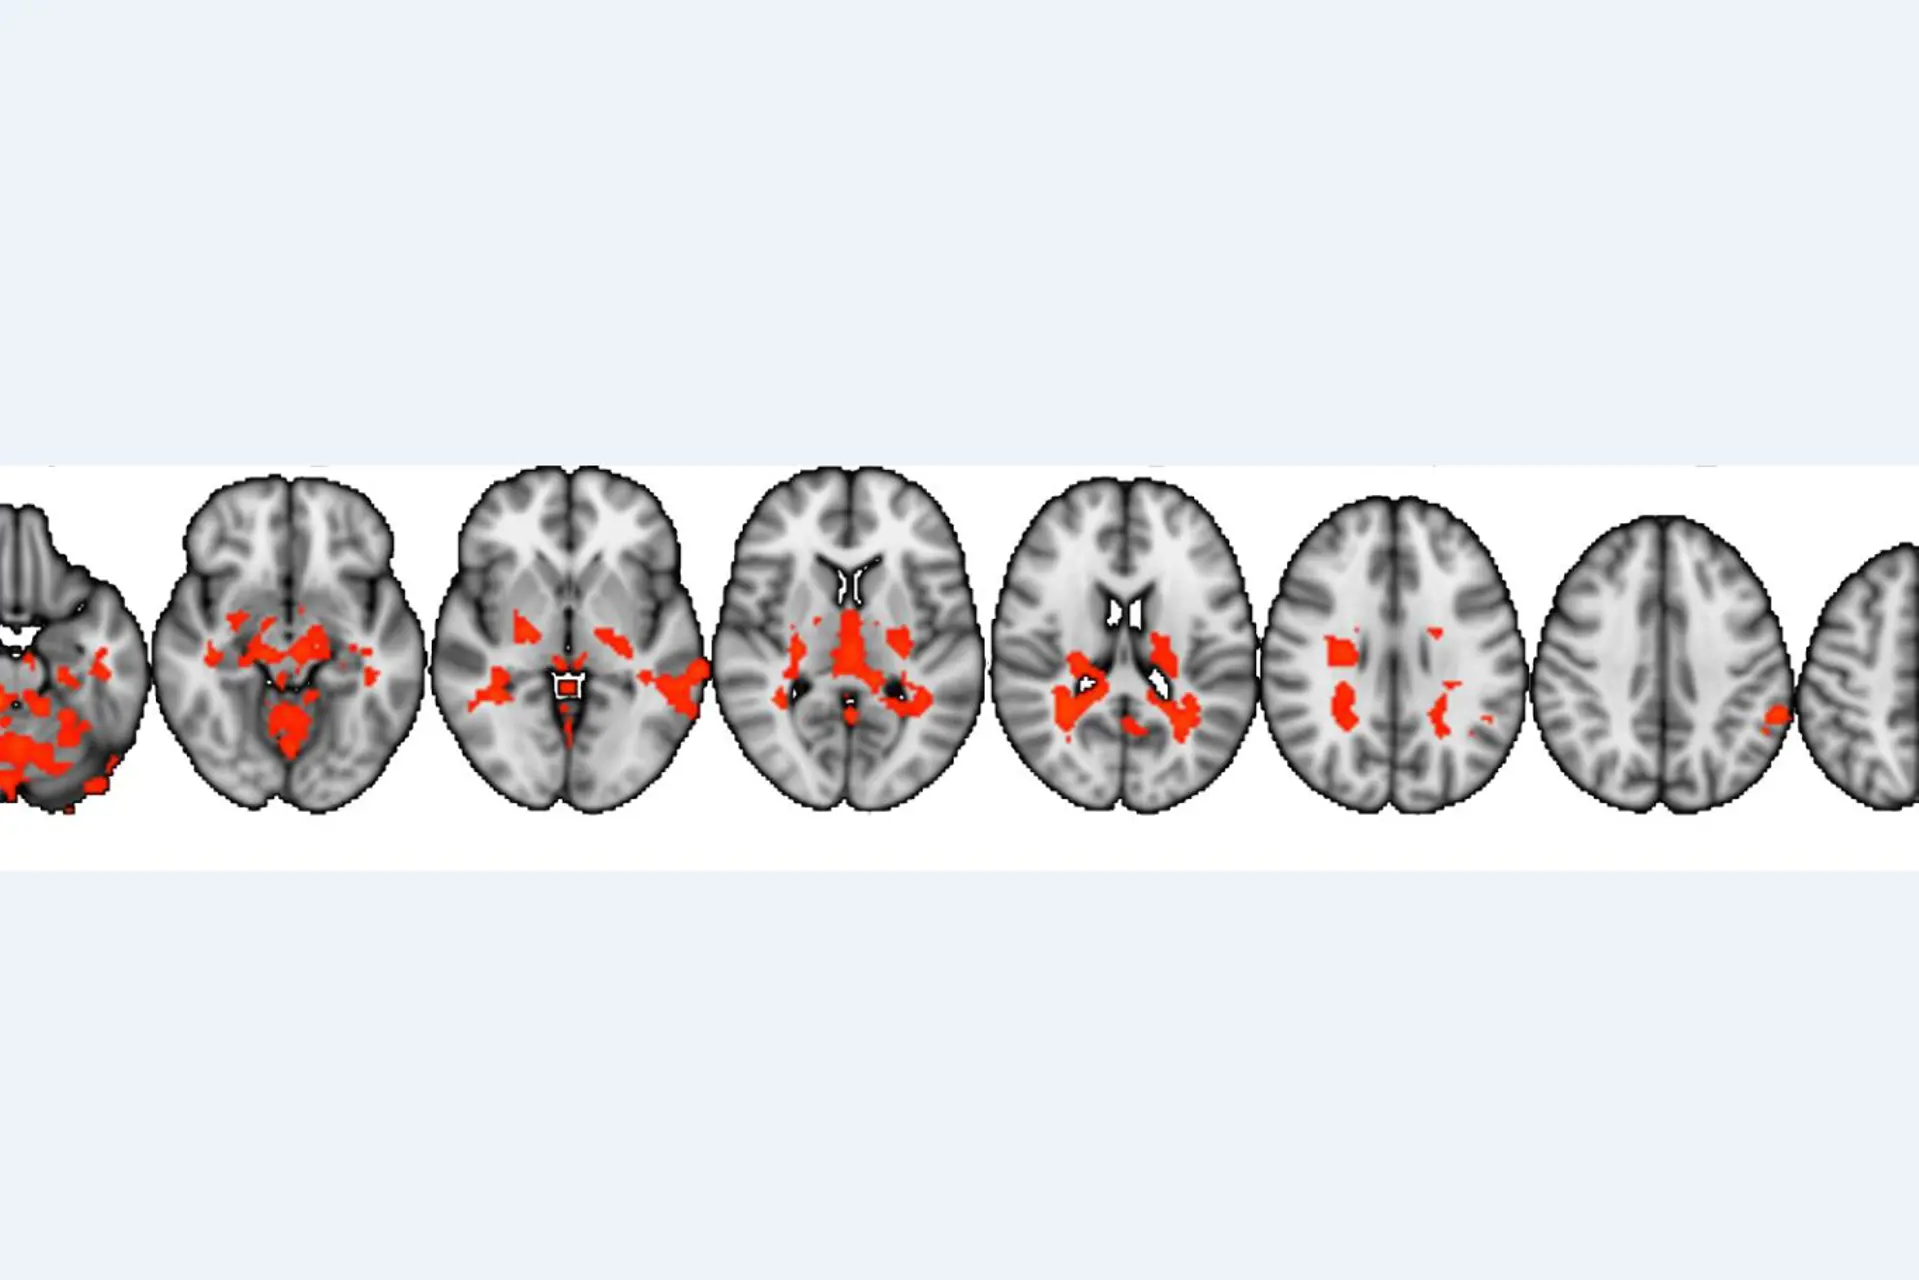

Figur fra studie: På figuren kan man se de områdene i hjernen som er mer aktive hos pasientene når de ser på filmer som de ikke selv syns er morsomme sammenlignet med slektningene deres.

Resultatene viser at narkolepsipasientene har annerledes hjerneaktivering når de ser på filmer som de ikke syns er morsomme sammenlignet med sine slektninger. De filmene som pasientene ikke selv syns er morsomme kan allikevel være potensielt morsomme og inneholde en «morsom punchline», og kan oppfattes som morsomme av andre.

Funnet tolkes derfor som om pasientene har en «overaktivering» under potensielt morsomme filmer selv om de ikke selv syns filmene er morsomme, ettersom hjerneaktiveringen ser lik ut uavhengig av om de syns filmene er morsomme eller ikke. Dette er i motsetning til slektningene deres som har aktivering i flere områder når de ser på filmer de syns er morsomme sammenlignet med filmer de ikke syns er morsomme. Det var ingen forskjell i hjerneaktiveringen mellom pasienter og slektninger når de så på de 5 filmene som manglet den «morsomme punchlinen».